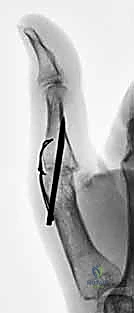

- DIP Joints and Thumb Interphalangeal Joint: These joints should generally be fused in 0 to 10 degrees of flexion. This allows for optimal tip-to-tip pinch and avoids impingement during grasp.

Figure 1: Recommended positions for digital joint fusion.

* PIP Joint:

* Some authors recommend a uniform 40-degree flexion position for all digits.

* Others recommend a cascade: 40 degrees for the index finger, progressing ulnarward in 5-degree increments to 55 degrees in the small finger.

* Clinical Pearl: Many surgeons prefer a slightly more extended position for the index PIP (e.g., 30-35 degrees) to optimize tip-to-tip pinch, which is crucial for this digit.

* Digital MCP Joints (Digits 2-5): The recommended fusion angle is a cascade from 25 degrees of flexion in the index digit, progressing ulnarward in 5-degree increments to 40 degrees in the small finger.

* Thumb MCP Joint: The recommended fusion angle is 10 to 15 degrees of flexion. This provides stability for pinch and power grip without hindering the crucial IP and CMC motion.